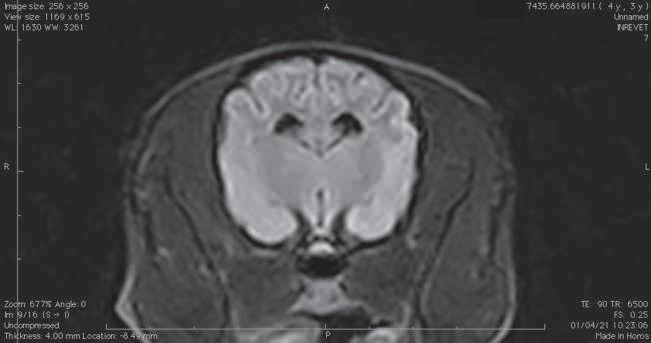

Figura 1. (A y C) Imágenes ponderadas en T2W. (B y D) FLAIR con lesiones hiperintensas en múltiples regiones encefálicas asociados a focos de edema con mayor evidencia en núcleos basales y tálamo (A, B) y lóbulos parietales y temporales (C y D).

A B C D

Figura 2. Imágenes ponderadas en T2W (A, C) y FLAIR (B, D) en las cuales se aprecia una disminución en las lesiones hiperintensas descritas en la figura 1.

Conbasealosresultadosderesonancia magnética (Figura 1), raza y hallazgos neurológicos los pacientes fueron diagnosticados con enfermedad inflamatoria cerebral (Meningoencefalitis de origen desconocido) e iniciaron con una terapia basadaenStee2020,10 conlacombinación decitarabina(Cytosar-U®Pfizer500mg) a dosis de 100/m2 y prednisona a dosis de 1 mg/kg iniciales por 4 semanas (dosis reducción a 36 semanas), para posteriormente evaluar la evolución clínica del paciente y por imagen con las mismas indicaciones de resonancia previamente descritas.

En el presente estudio 5 de 6 pacientes mostraronunamejoracínicasignificativa, enunpaciente(Shih-tzu)elcualingresóen estatus epiléptico no presentó más crisis convulsivas ni se han reportado hasta el momento, el estado mental de los 6 pacientes mejoró de forma significativa, sólounpaciente(Yorkshire)conimágenes por resonancia magnética con herniación subfalcina continuó con giros, los déficits propioceptivos continuaron en 2 de 6 pacientes (Cuadro 3). En las imágenes por resonancia magnética posterior a las 4 semanas iniciado el tratamiento se vio unadisminucióndeledemareportadoque va desde el 85% hasta 50% (Figura 2).